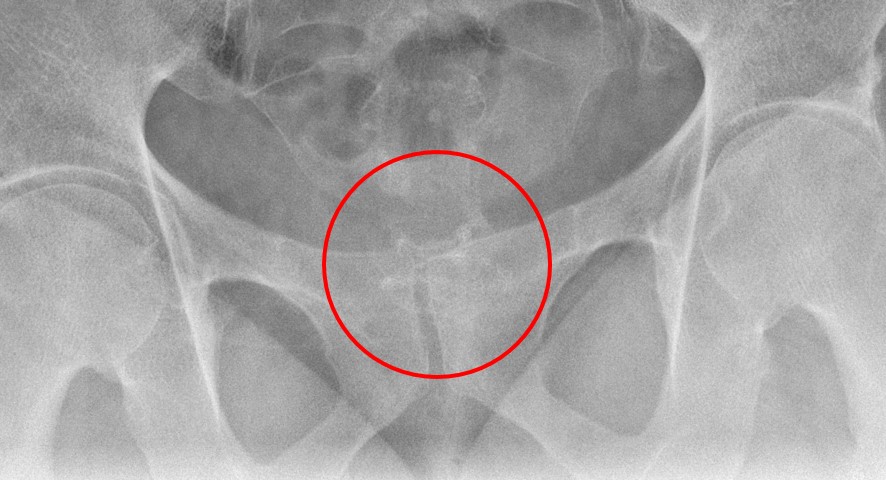

- During this examination, special attention should be paid to the anatomosis. When reviewing the scout image, look for surgical chain sutures in the pelvis

(key image 20)

(key image 21).